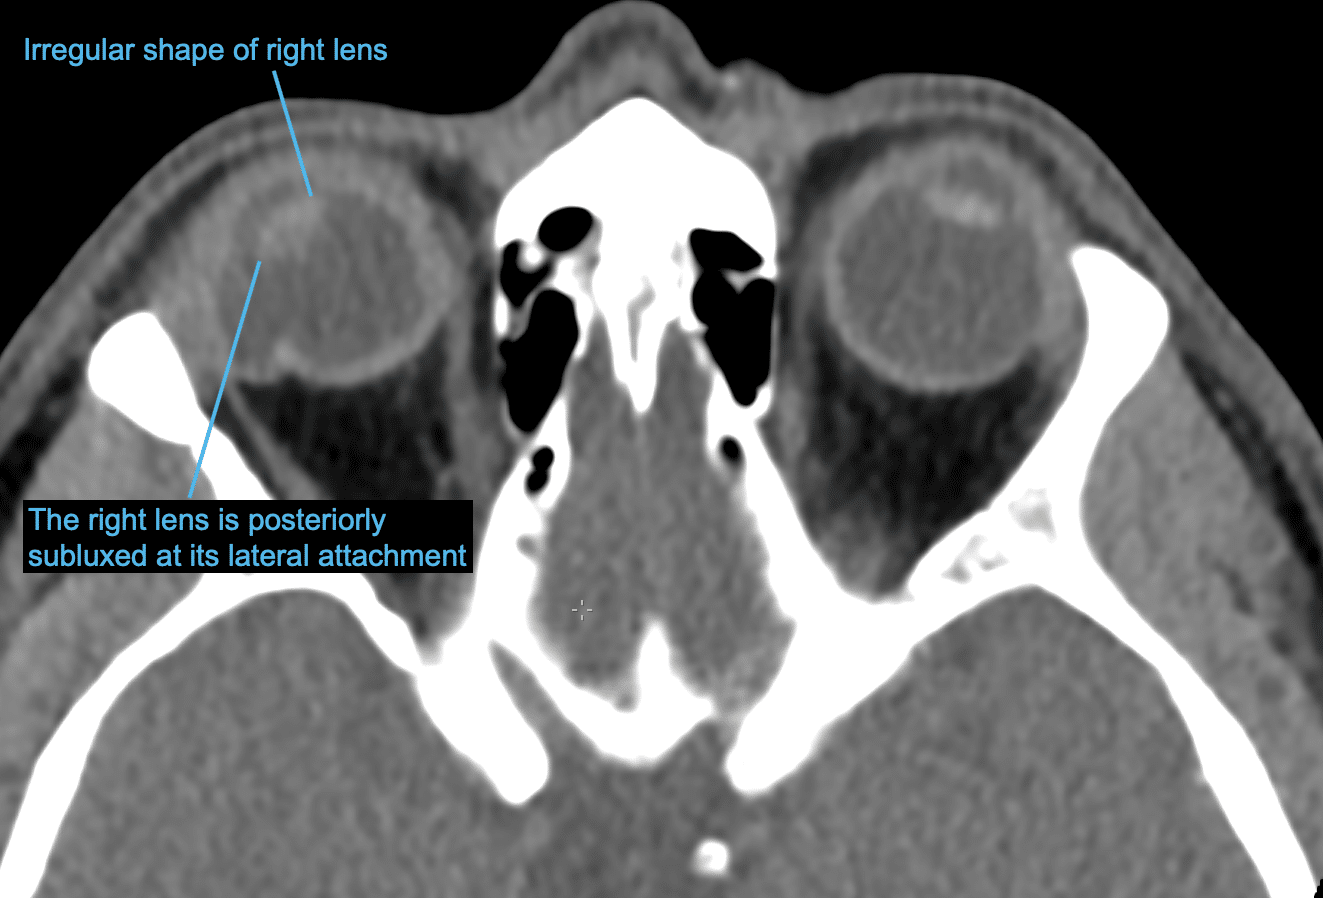

Dislocated lens of the eye, CT scan Stock Image F036/7464 Science Lens Replacement On Ct On ct, the keratoprosthesis plastic front plate that functions as a lens appears as soft tissue attenuation alongside the higher attenuation titanium locking back plate and locking. A primary understanding of the globe. Eye lens replacement is an outpatient surgery in which an ophthalmologist removes your eye’s natural lens and implants an intraocular. Imaging after cataract surgery and phakic intraocular. Lens Replacement On Ct.